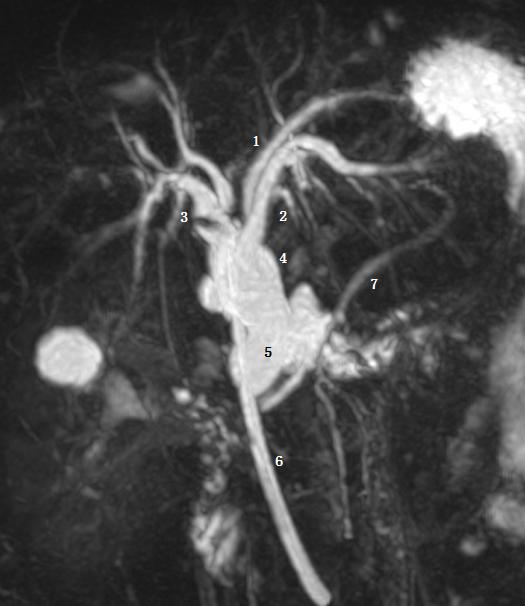

Ⅲb 型为右后肝管汇入肝总管。图 1 为右前肝管,2 为肝左管,3 为右后肝管,4 肝总管,5 胆囊管,6 胆总管。

Ⅴ型为副肝管的存在。图示 1 为肝右管,2 为肝左管,3 为副肝管,4 为肝总管,5 为胆囊管,6 为胆总管。

Ⅵ型为 2、3 段分级肝管汇入右肝管或肝总管。图为胆总管末端梗阻 T 管引流术后。图示 1 为 2 段肝管,2 为 3 段肝管,3 为肝右肝管,4 为肝总管,5 为胆总管,6 为 T 型管,7 胰管。